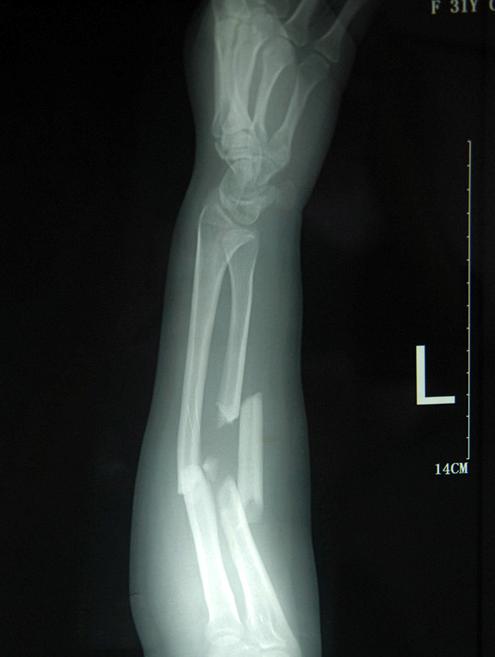

粉碎性的骨折多久才能愈合?一般情况的四肢粉碎性的骨折,至少需要3个月或者以上的时间才能正常愈合的。并且这还和骨折伤处的血液供应的状况、软组织损伤的程度、身体健康的情况、康复治疗的方法都是有一定关系的。